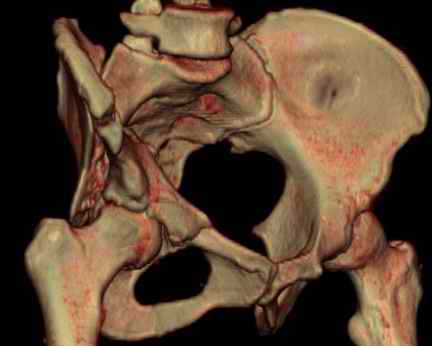

Посылаю схемы и 3D реконструкцию подобного повреждения. Называется он полным высоким двухколонным переломом вертлужной впадины, а "переломы крыла и тела подвздошной кости" входят в это понятие.

1 закрытая репозиция аппаратом + фиксация через проколы винтами

2 закрытая репозиция передней колонны + открытая задней колонны из задне-неружного доступа

3 открытая репозиция передней колонны из подвздошнго доступа + открытая задней колонны из задне-наружного доступа

4 открытая репозиция из илиоингвинального доступа

5 открытая репозиция из Y образного доступа

Я бы ориентировался на Y образный доступ

или из двух если есть сомнения в целостности задних отделов крыла.

прикладываю схему доступа и случай.

Одним задне наружным переднюю колонну не достать, а илио-ингвинальный более сложный не позволяет контролировать суставную поверхность и трудно управлять задней колонной.